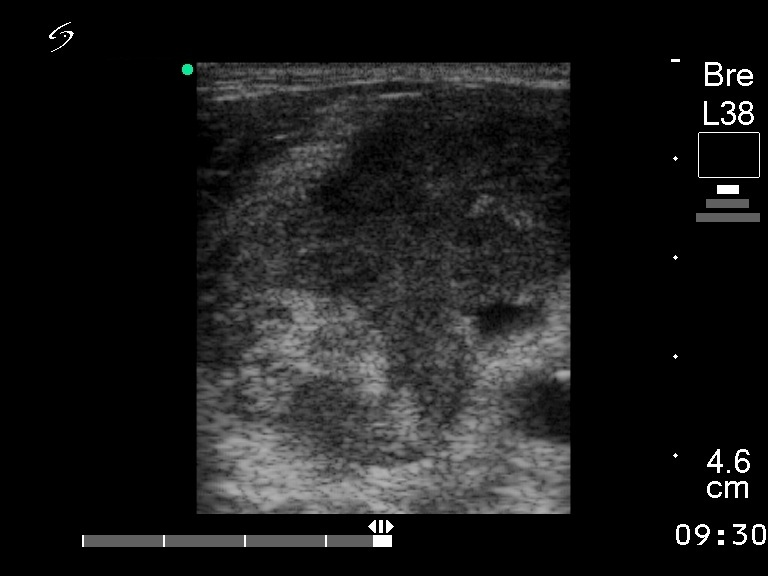

Ultrasonography. The right lobe was enlarged and consisted of multiple hypoechogenic nodules. Multiple enlarged lymph nodes were detected on the right side of the neck.